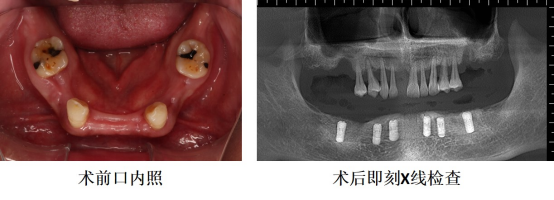

2026年1月19日,手术在周密筹备下如期开展。口腔种植团队凭借精准的术前规划和娴熟的技术操作,高效完成了病灶牙微创拔除、种植体精准植入及骨增量手术。整个手术历时三小时,过程流畅,患者生命体征始终保持平稳。此次协作不仅体现了技术上的无缝衔接,更展现了在患者安全这一共同目标下,学科间的高度信任与责任共担。